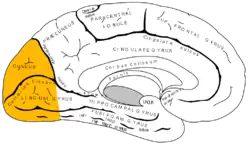

The lobes rest on the tentorium cerebelli, a process of dura mater that separates the cerebrum from the cerebellum. They are structurally isolated in their respective cerebral hemispheres by the separation of the cerebral fissure. At the front edge of the occipital lobe are several occipital gyri, which are separated by lateral occipital sulcus.

The occipital aspects along the inside face of each hemisphere are divided by the calcarine sulcus. Above the medial, Y-shaped sulcus lies the cuneus, and the area below the sulcus is the lingual gyrus.

Retinal sensors convey stimuli through the optic tracts to the lateral geniculate bodies, where optic radiations continue to the visual cortex. Each visual cortex receives raw sensory information from the outside half of the retina on the same side of the head and from the inside half of the retina on the other side of the head. The cuneus (Brodmann's area 17) receives visual information from the contralateral superior retina representing the inferior visual field. The lingula receives information from the contralateral inferior retina representing the superior visual field. The retinal inputs pass through a "way station" in the lateral geniculate nucleus of the thalamus before projecting to the cortex. Cells on the posterior aspect of the occipital lobes' gray matter are arranged as a spatial map of the retinal field. Functional neuroimaging reveals similar patterns of response in cortical tissue of the lobes when the retinal fields are exposed to a strong pattern.